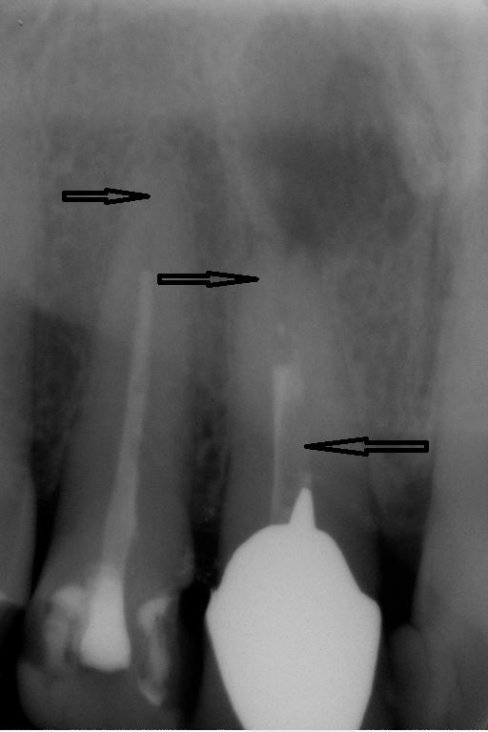

Fallbeispiel für einen Seitenrand

Fallbeispiel für einen komplexen Kanalverlauf

Fallbeispiel für eine große Entzündung an der Wurzel

Wurzel nach erfolgreicher Behandlung 2 Monate später schon fast ausgeheilt